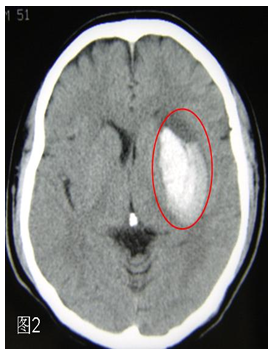

在某些地方也把头颅CT更形象地称作“脑扫描”。CT可以在最快的时间内了解,因为脑动脉堵塞而发生了脑梗死还是脑动脉破裂而出现了脑出血。脑梗死时头颅CT发现在脑组织出现了片状的黑色图像(图1),脑出血时可见在脑组织中出现了白色的团块(图2),一目了然。所以,得了脑卒中,第一要做的检查就是头颅CT。